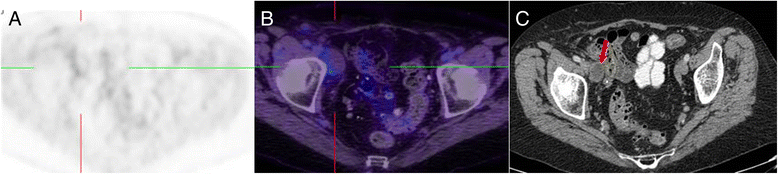

This patient had suspicion of pelvic recurrence in the setting of prior surgical excision for rectal carcinoma. There was intense uptake in the known pre-sacral soft tissue thickening (a) and (c) (red arrow) with SUVmax of 11. The linear morphology on the coronal image (b) suggested this was more likely inflammatory than malignant. A separate linear tract of metabolic activity was also seen (green arrow) extending from the pre-sacral abnormality to the peri-anal region (not shown). All abnormalities resolved following antiobiotic therapy confirming inflammatory aetiology